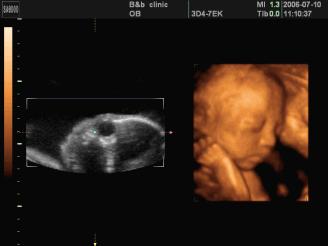

是立体动态显示的彩色多普勒超声诊断仪,可以进行胎儿头面部立体成像,可显示眼、鼻、口、下颌等状态,协助医生直接对胎儿先天畸形进行诊断,价格比普通彩超价格贵。

●四维彩超

四维彩超能够对胎儿进行动态、立体超声检查,显示胎儿的面部、各器官的发育情况,甚至胎儿在母体里的状态也可以观察到;对胎儿畸形,如唇裂、腭裂、骨骼发育异常等能早期诊断。另外还能制作成光盘,让宝宝拥有最完整的0岁相册,留下永久的记忆。